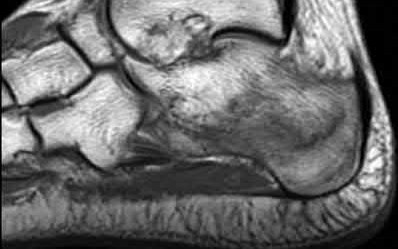

A 25-year-old male sustains an ankle fracture dislocation and undergoes open reduction and internal fixation. He returns to clinic five months following surgery complaining of continued ankle pain and instability with weight bearing. His immediate post-operative AP radiograph is seen in Figure A. Which of the following could have prevented this patient from developing persistent pain?

The patient presents with continued ankle pain and instability following open reduction and internal fixation. The radiograph in figure A demonstrates inadequate restoration of fibular length, likely leading to continued tibiotalar instability.